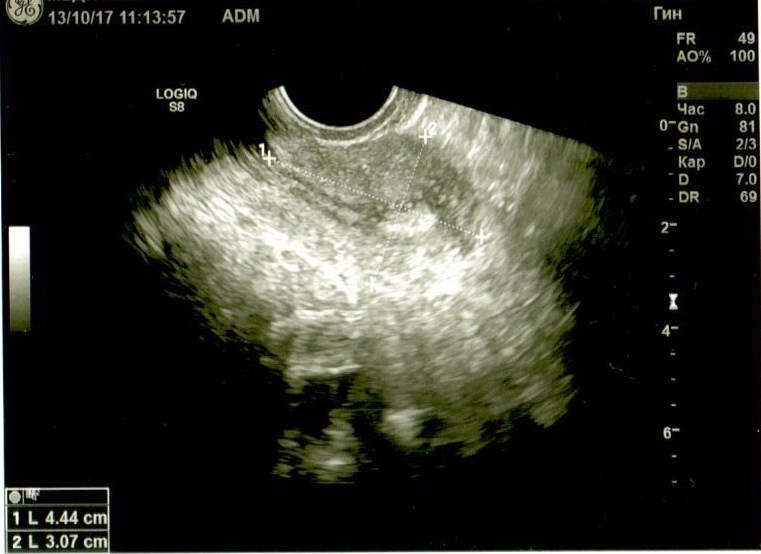

Если можно, посмотрите. Буду очень благодарна. Не очень в этом разбираюсь, поэтому выкладываю все снимки и заключение узистки.

Добрый день! У Вас в самой структуре яичника имеются гиперэхогенные включения, которые говорят о перенесенном воспалении, при этом о спайках может говорить только расположение яичников возле матки ( это если опираться на описание, так как на фото не видно). Однозначно, имеет место хронический оофорит. И в эндометрии мне не нравится зона в области дна. Врач ее даже выделила, но не описала. Эндометрий неоднородный, стоит сделать УЗИ на 5 день цикла повторно.

Спасибо большое! У меня эндометрий тонкий, сейчас как раз лечим. Вопрос: Вы пишите "при этом о спайках может говорить только расположение яичников возле матки", так а где им еще находиться? Узистка написала, что расположены оба яичника правильно...